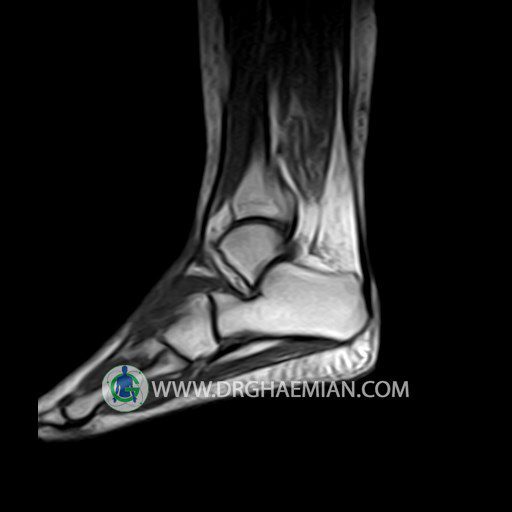

پزشکان اغلب از تصویربرداری ام آر آی برای تشخیص و درمان عارضه های پزشکی که فقط با استفاده از اشعه ایکس یا میدان مغناطیسی و امواج رادیویی قابل مشاهده است، استفاده می کنند. دستگاه ام آر آی تصاویر دقیق از ساختار های داخلی بدن ایجاد می کند. در این کیس تورم مچ پا بیمار مشاهده می شود.

– Mild soft tissue swelling around the knee

is seen